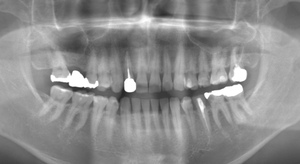

セラミックインレーと

ジルコニアインレーの症例

Before

部位拡大写真

After

基本情報

| 年齢・性別 | 40代・女性 |

|---|---|

| 主訴 | 虫歯気になる 全体的に銀歯をやりかえたい 右上4567 |

| 治療内容 | セラミックインレー(右上456番) ジルコニアインレー(右上7番) |

| 治療費 | 209,000円 (セラミックインレー1本55,000円) (ジルコニアインレー1本44,000円) |

| 治療期間 | 約2週間 |

| リスク・副作用 | ジルコニアインレーは硬いため噛み合わせの歯を傷付ける可能性がある |